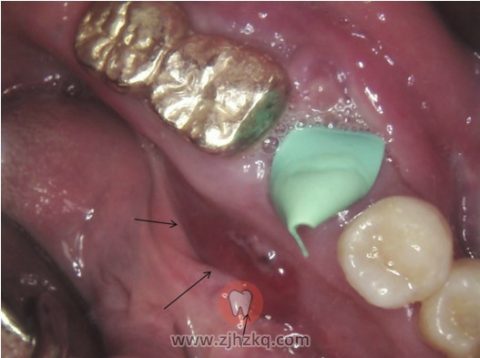

一名75岁男子从当地诊所转诊到京熙牙科医院,以评估左下唇感觉异常和左颊坚韧肿块的情况。他的左下颌骨部位有轻微肿胀。触诊感觉肿胀发硬,附着于下颌骨,并有轻微的触痛。左下唇感觉异常。口内检查发现舌前庭区域有较大的红斑(图1)。触诊未发现区域淋巴结。无特殊疾病史。根据患者的牙科病史,7个月前左下磨牙区钝痛,后因根尖周脓肿拔除左下第一磨牙(图2A)。患者在拔牙后约4个月接受了种植手术(图2B)。两个月后,因种植体周围炎移除种植体。之后,他感觉持续的钝痛、左下颌骨肿胀,以及左下唇麻木。全景片显示从左下前磨牙区到第二磨牙区不明确的浸润性骨质破坏。与他第一次在当地就诊获得的全景片(图2A)相比,病变已扩展至下颌管内(图3A)。根尖周见浸润性骨质破坏,软组织影增大(图3B)。锥束计算机断层扫描(Cone-beam computed tomography, CBCT)获得更详细的病变信息。矢状位图像显示左侧下颌体区溶骨性破坏,下颌管皮质脱落(图4A)。在横断面上,颊侧和舌侧皮质板有部分穿孔和侵蚀(图4B)。首次活检是在局部麻醉下进行的。组织病理学检查发现不典型浆细胞样细胞(图5A)。免疫组化显示肿瘤细胞中B细胞标记物CD20阴性(图5B),但浆细胞标记物CD138表达阳性(图5C)。而所有肿瘤细胞中均表达kappa轻链(图5D),不表达λ轻链,说明肿瘤细胞群体为单克隆细胞。最终诊断为孤立性浆细胞瘤。病人目前正在接受放射治疗。

图1.在舌前庭区域可见增大的红斑块(箭头)。